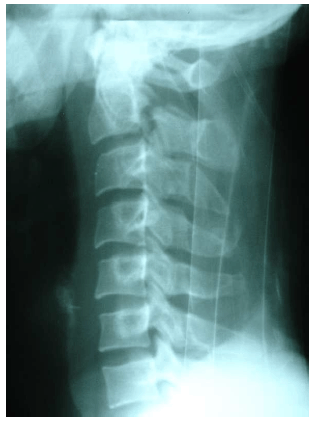

Dadas as afirmativas quanto à imagem radiográfica,

I. Trata-se de uma fratura em C3.

II. Observa-se uma fratura em C2.

III. A imagem radiológica permite avaliar que a fratura aconteceu na lâmina do arco vertebral.

IV. A imagem radiográfica apresenta uma lesão no pedículo do arco vertebral, comprometendo o nervo espinal C3.

verifica-se que está(ão) correta(s)